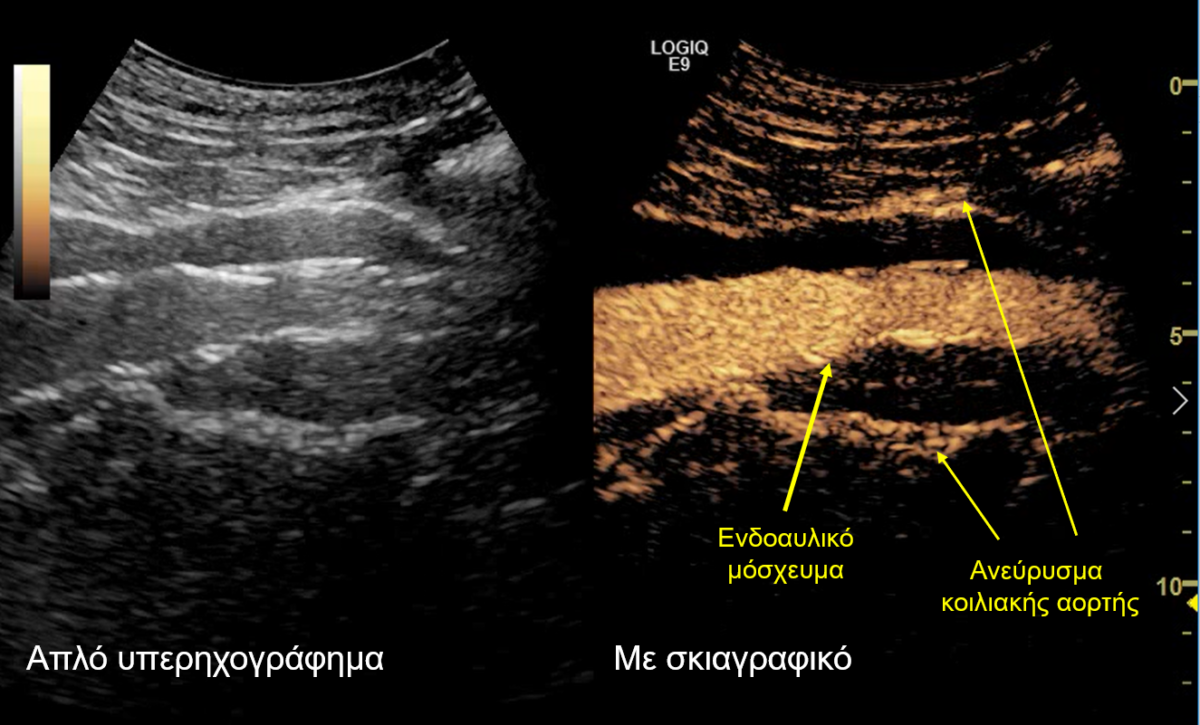

Σε αυτό το πλαίσιο εντάσσεται και ο μετεγχειρητικός υπερηχογραφικός έλεγχος που διεξήχθη στο Τμήμα Υπερήχων από τη Δρ. Κωνσταντίνα Κυριακοπούλου, MD, PhD,  Διευθύντρια Τμήματος Υπερήχων, Ιατρικό Κέντρο Αθηνών και τον Ταξιάρχη Καράμπελα, MD, Ακτινολόγο, Αναπληρωτή Διευθυντή Τμήματος Υπερήχων, Ιατρικό Κέντρο Αθηνών. Το κέντρο αυτό ανήκει στα ελάχιστα ευρωπαϊκά κέντρα, τα οποία ελέγχουν τη βατότητα των σπλαγχνικών αγγείων και την επιτυχή ενδοαγγειακή αποκατάσταση των ανευρύσματων υπερηχογραφικά, με τη χρήση ειδικού σκιαγραφικού (SonoVue) που μεταβολίζεται αποκλειστικά στο ήπαρ. Αυτό αποτελεί ιδιαίτερο πλεονέκτημα σε ασθενείς με επηρεασμένη νεφρική λειτουργία.